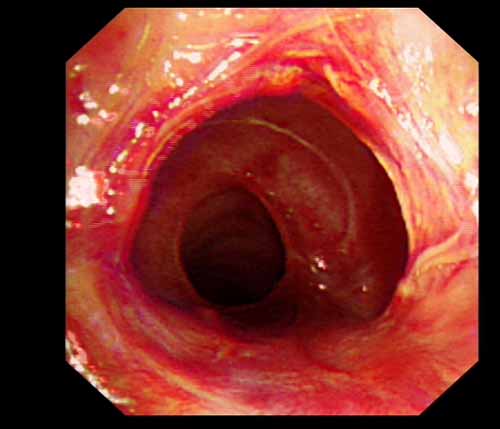

患者李某某,女,45歲,因氣管插管咳嗽、喘憋10天入院。頸部CT檢查示聲門下約20mm處氣管明顯狹窄,狹窄段長(zhǎng)約26mm,最窄處直徑約4.4mm。支氣管鏡檢查見(jiàn)聲門下約2cm氣管呈漏斗狀縮窄,直徑約4-5mm,支氣管鏡無(wú)法通過(guò)。經(jīng)科室討論,決定行電子支氣管鏡下氣管球囊擴(kuò)張治療。與患者及家屬充分溝通并經(jīng)三方見(jiàn)證談話簽署知情同意書(shū)后,在患者持續(xù)吸氧、局麻下,科主任于世倫主任醫(yī)師帶領(lǐng)治療小組為患者實(shí)行電子支氣管鏡下氣管球囊擴(kuò)張術(shù)。手術(shù)過(guò)程順利,出血量很少,術(shù)后患者呼吸困難癥狀即可明顯緩解。10天后行二次擴(kuò)張,患者日常活動(dòng)無(wú)明顯喘憋,二次術(shù)后5天出院。

術(shù)后擴(kuò)張開(kāi)的氣管管腔